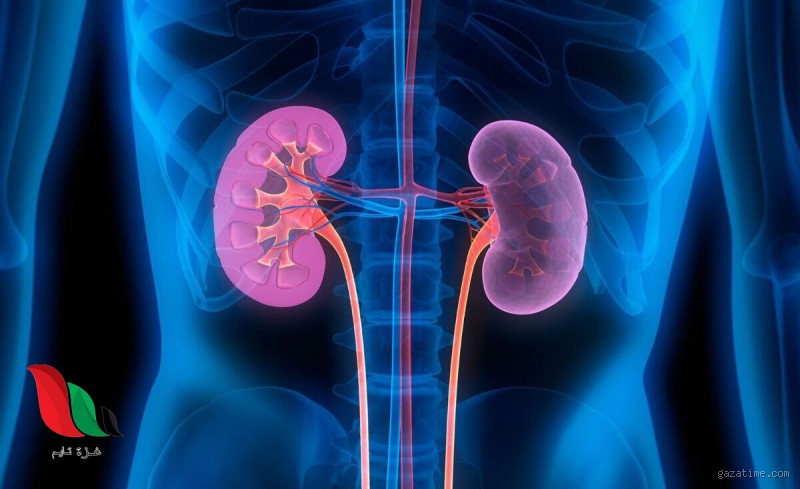

Well, أعتقد أنك قد تساءلت يومًا: أين يكون ألم الكلى في جسم الإنسان؟ إذا كنت قد عانيت من ألم في أسفل الظهر أو الجانب، فقد يكون لديك فكرة عن هذا النوع من الألم. لكن الكلى قد تسبب آلامًا في مناطق مختلفة من الجسم، وليس فقط في الظهر كما يعتقد البعض. دعني أخبرك بكل التفاصيل حول ألم الكلى وأين يمكن أن يظهر في جسمك.

بصراحة، ألم الكلى في جسم الإنسان يشعر وكأنه ضغط أو ألم شديد في أسفل الظهر أو الجنب. لو كنت قد شعرت بهذا الألم من قبل، فربما قد شعرت بأن هناك شيء ثقيل يقع على جانبك. عادة، يكون الألم في المنطقة التي تقع أسفل القفص الصدري مباشرة، على جانبي الظهر.

وأتذكر مرة كان أحد أصدقائي يعاني من ألم حاد في الجنب، وقال لي إنه كان يشعر وكأن هناك شيء يضغط عليه. في البداية، اعتقدنا أنه مجرد تعب عضلي، لكن بعد زيارة الطبيب، اكتشفنا أنه كان ألمًا مرتبطًا بالكلى بسبب حصى الكلى. هذا النوع من الألم يمكن أن يكون شديدًا جدًا، أحيانًا لدرجة أنه قد يصعب عليك الوقوف أو الجلوس براحة.

لكن انتظر، ليس دائمًا الألم يكون محصورًا في الظهر. في بعض الأحيان، قد يمتد ألم الكلى إلى مناطق أخرى من الجسم مثل البطن أو حتى الفخذ. في حالتي الشخصية، شعرت في مرة بألم في الجانب الأيسر من البطن، وكان أشبه بألم حاد يرافقه شعور غريب بالضغط. كنت أتوقع أنه مجرد تعب في المعدة، ولكن الطبيب أخبرني أن الكلى قد تكون السبب في ذلك.

Honestly, قد يكون من الصعب أحيانًا التمييز بين ألم الكلى وألم الظهر العادي. إذا كنت تعاني من ألم الظهر المعتاد بسبب الجلوس الطويل أو النوم بطريقة غير صحيحة، قد تشعر بألم في الجزء السفلي من الظهر فقط. ولكن إذا كان الألم يمتد إلى أسفل البطن أو يمتاز بالحِدة والضغط الشديد في جانبك، فقد يكون هذا علامة على مشكلة في الكلى.

الألم الناتج عن مشاكل الكلى عادة ما يصاحبه أعراض أخرى مثل الغثيان، القيء، التبول المؤلم، أو حتى تغير في لون البول (مثل أن يصبح البول عكرًا أو يحتوي على دم). مرة أخرى، تذكرت كيف أن أحد أفراد عائلتي شعر بالغثيان الشديد مع ألم في الجنب، وعندما ذهب للطبيب، تبين أنه يعاني من التهاب في الكلى.

في النهاية، عندما تشعر بألم في الكلى، يجب أن تكون منتبهًا للمكان الذي يظهر فيه الألم والأعراض المصاحبة له. قد يكون الألم في أسفل الظهر أو الجنب، أو قد يمتد إلى البطن والفخذ. إذا كنت تشك في أن الألم مرتبط بالكلى، فمن الأفضل أن تستشير الطبيب في أسرع وقت. لا تستهين بالألم، خاصة إذا كان مستمرًا أو يتزايد، لأن الكشف المبكر يمكن أن يحميك من مضاعفات أكبر.